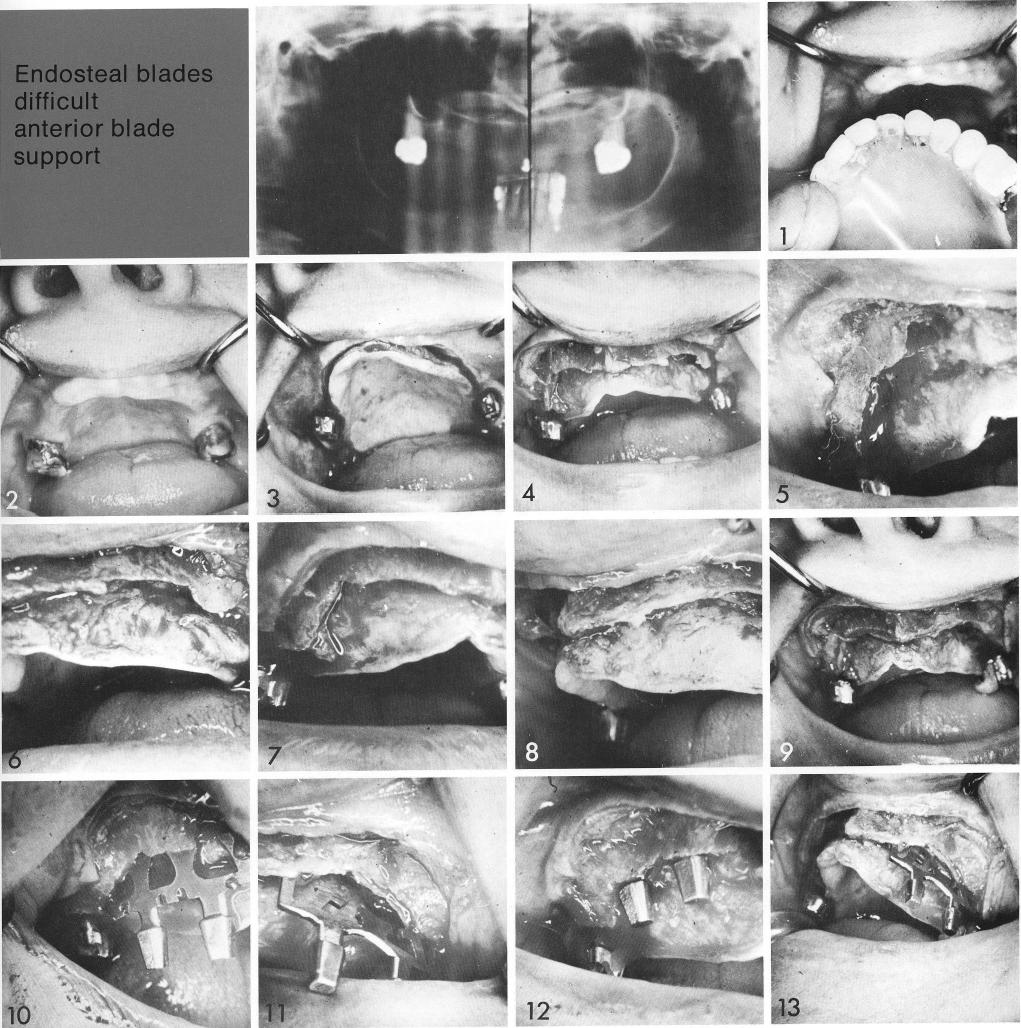

Endosteal blade

difficult

anterior blade support

1 Maxillary ridge needs considerable work before using bladevent implants